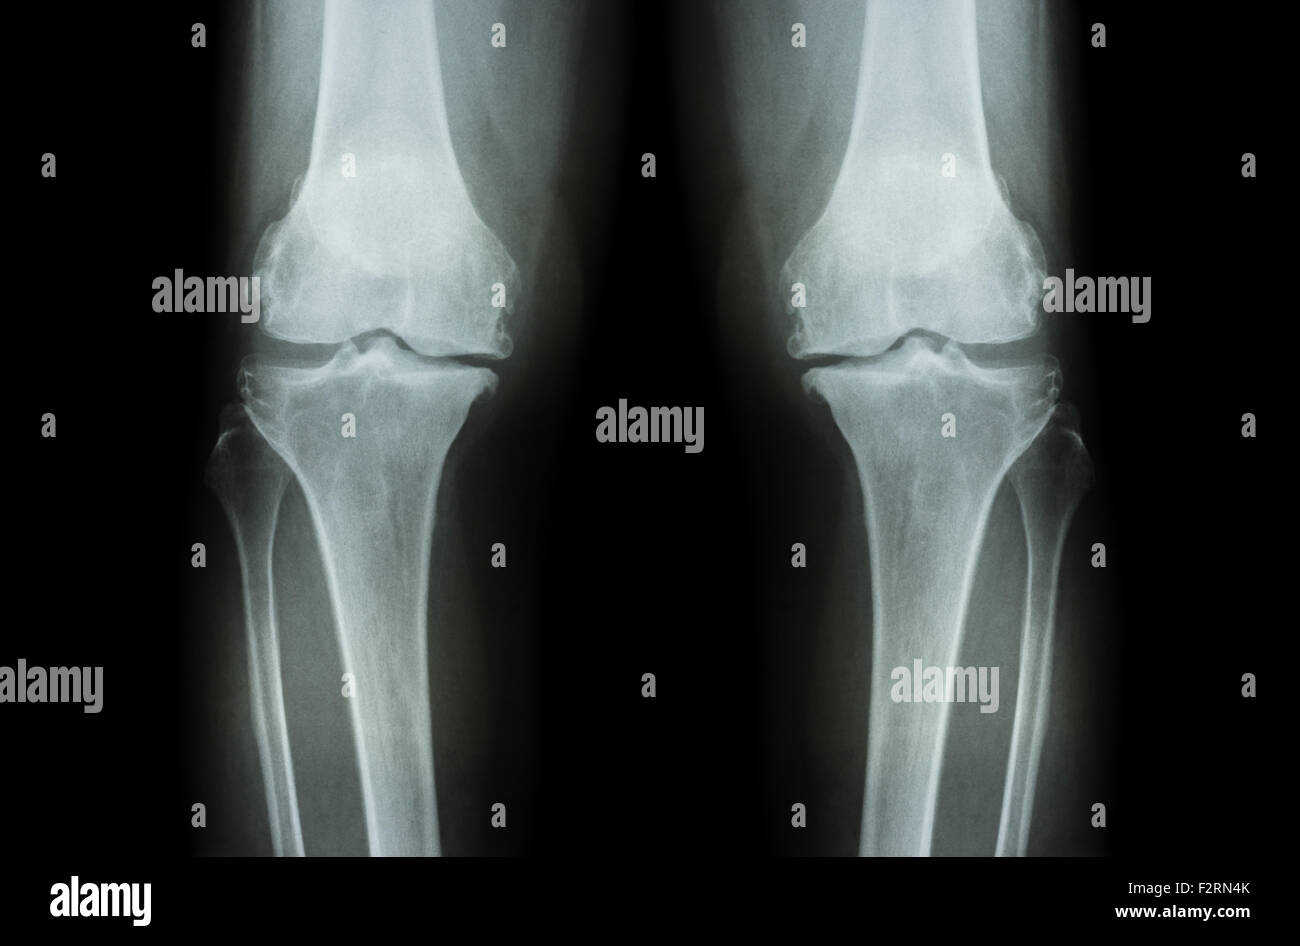

L'ARTHROSE DU GENOU Arthrose du genou ( ). Film x-ray deux genou ( vue avant ) show spatial commun étroit ( perte de cartilage ) , osteophy Banque D'Imageshttps://www.alamyimages.fr/image-license-details/?v=1https://www.alamyimages.fr/photo-image-l-arthrose-du-genou-arthrose-du-genou-film-x-ray-deux-genou-vue-avant-show-spatial-commun-etroit-perte-de-cartilage-osteophy-87802628.html

L'ARTHROSE DU GENOU Arthrose du genou ( ). Film x-ray deux genou ( vue avant ) show spatial commun étroit ( perte de cartilage ) , osteophy Banque D'Imageshttps://www.alamyimages.fr/image-license-details/?v=1https://www.alamyimages.fr/photo-image-l-arthrose-du-genou-arthrose-du-genou-film-x-ray-deux-genou-vue-avant-show-spatial-commun-etroit-perte-de-cartilage-osteophy-87802628.htmlRFF2RN44–L'ARTHROSE DU GENOU Arthrose du genou ( ). Film x-ray deux genou ( vue avant ) show spatial commun étroit ( perte de cartilage ) , osteophy

L'ARTHROSE DU GENOU Arthrose du genou ( ). Film x-ray deux genou ( vue avant ) show spatial commun étroit ( perte de cartilage ) , osteophy Banque D'Imageshttps://www.alamyimages.fr/image-license-details/?v=1https://www.alamyimages.fr/photo-image-l-arthrose-du-genou-arthrose-du-genou-film-x-ray-deux-genou-vue-avant-show-spatial-commun-etroit-perte-de-cartilage-osteophy-87802655.html

L'ARTHROSE DU GENOU Arthrose du genou ( ). Film x-ray deux genou ( vue avant ) show spatial commun étroit ( perte de cartilage ) , osteophy Banque D'Imageshttps://www.alamyimages.fr/image-license-details/?v=1https://www.alamyimages.fr/photo-image-l-arthrose-du-genou-arthrose-du-genou-film-x-ray-deux-genou-vue-avant-show-spatial-commun-etroit-perte-de-cartilage-osteophy-87802655.htmlRFF2RN53–L'ARTHROSE DU GENOU Arthrose du genou ( ). Film x-ray deux genou ( vue avant ) show spatial commun étroit ( perte de cartilage ) , osteophy

L'ARTHROSE DU GENOU Arthrose du genou ( ). Film x-ray deux genou ( vue avant ) show spatial commun étroit ( perte de cartilage ) , osteophy Banque D'Imageshttps://www.alamyimages.fr/image-license-details/?v=1https://www.alamyimages.fr/photo-image-l-arthrose-du-genou-arthrose-du-genou-film-x-ray-deux-genou-vue-avant-show-spatial-commun-etroit-perte-de-cartilage-osteophy-87802612.html

L'ARTHROSE DU GENOU Arthrose du genou ( ). Film x-ray deux genou ( vue avant ) show spatial commun étroit ( perte de cartilage ) , osteophy Banque D'Imageshttps://www.alamyimages.fr/image-license-details/?v=1https://www.alamyimages.fr/photo-image-l-arthrose-du-genou-arthrose-du-genou-film-x-ray-deux-genou-vue-avant-show-spatial-commun-etroit-perte-de-cartilage-osteophy-87802612.htmlRFF2RN3G–L'ARTHROSE DU GENOU Arthrose du genou ( ). Film x-ray deux genou ( vue avant ) show spatial commun étroit ( perte de cartilage ) , osteophy

L'ARTHROSE DU GENOU Arthrose du genou ( ). Film x-ray deux genou ( vue avant ) show spatial commun étroit ( perte de cartilage ) , osteophy Banque D'Imageshttps://www.alamyimages.fr/image-license-details/?v=1https://www.alamyimages.fr/photo-image-l-arthrose-du-genou-arthrose-du-genou-film-x-ray-deux-genou-vue-avant-show-spatial-commun-etroit-perte-de-cartilage-osteophy-87802643.html

L'ARTHROSE DU GENOU Arthrose du genou ( ). Film x-ray deux genou ( vue avant ) show spatial commun étroit ( perte de cartilage ) , osteophy Banque D'Imageshttps://www.alamyimages.fr/image-license-details/?v=1https://www.alamyimages.fr/photo-image-l-arthrose-du-genou-arthrose-du-genou-film-x-ray-deux-genou-vue-avant-show-spatial-commun-etroit-perte-de-cartilage-osteophy-87802643.htmlRFF2RN4K–L'ARTHROSE DU GENOU Arthrose du genou ( ). Film x-ray deux genou ( vue avant ) show spatial commun étroit ( perte de cartilage ) , osteophy